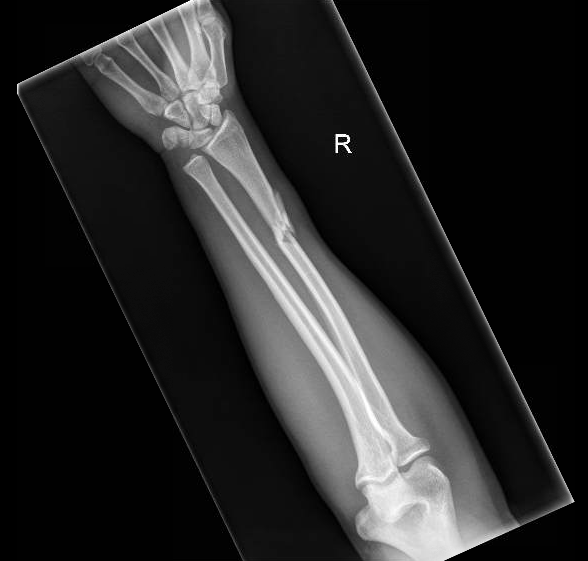

Galeazzi Fracture AP XRay JETem 2017

Galeazzi Fracture